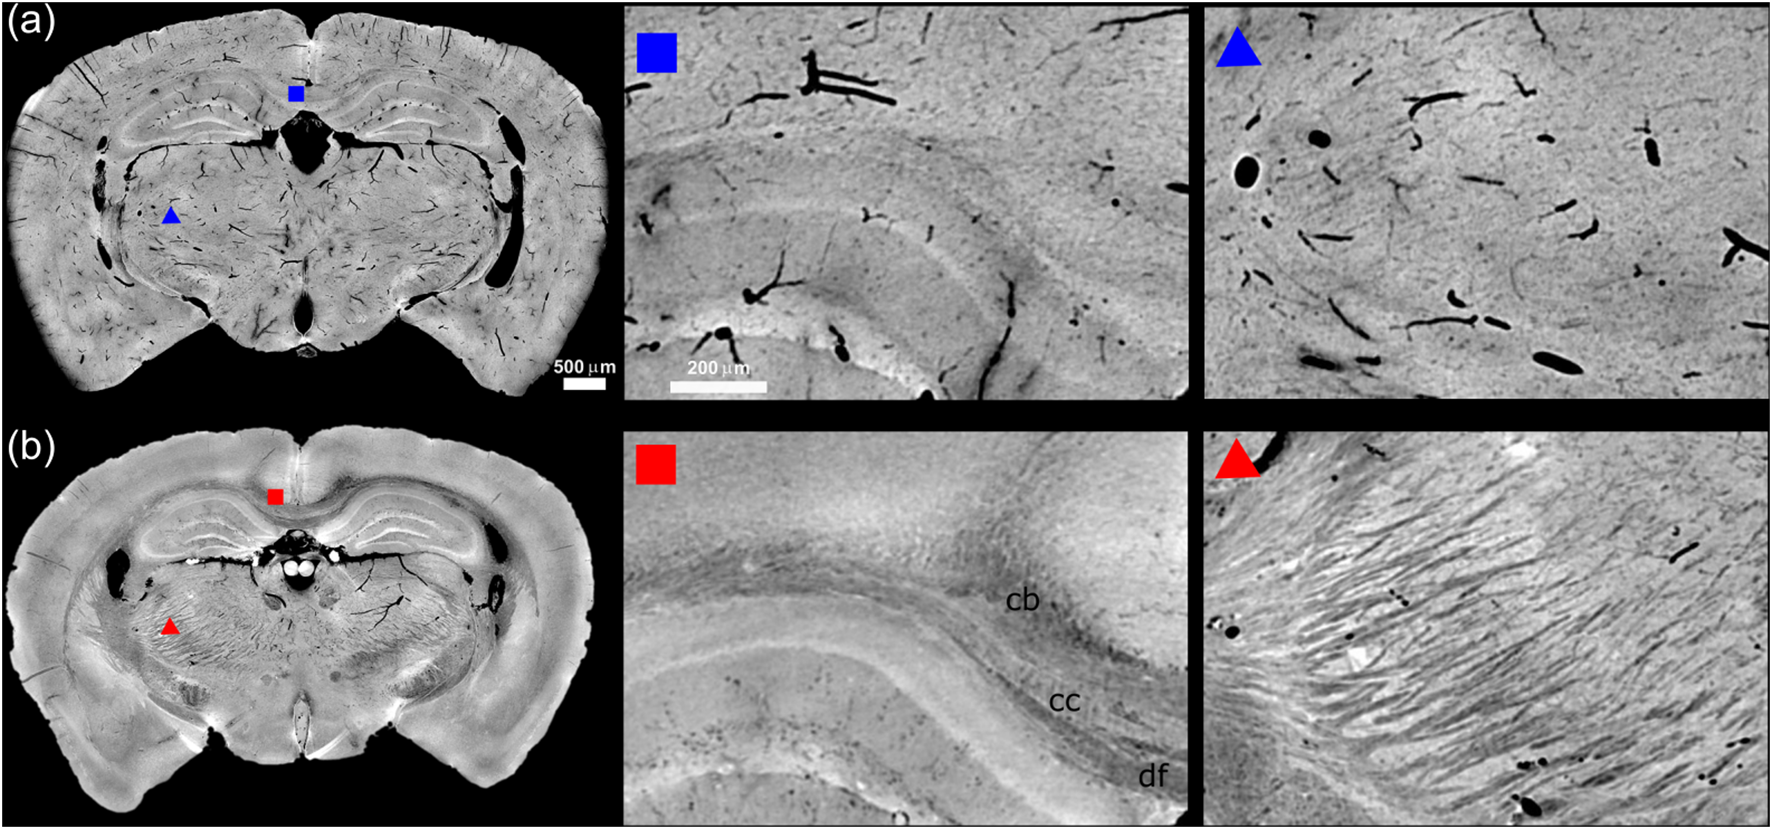

In order to discuss the various features detectable in the tomographic slices with several sample preparations, we report in Figures 1, 2 the XPCT reconstructions of the mouse brain and of the spinal cord (of the same sample) treated with ethanol and with xylene respectively (Figures 1A, 2A-C, 1B, 2D-H).

FIGURE 1

Panel (A, B) show a minimum intensity projection section across 45 μm of mouse midbrain following ethanol and xylene preparation protocols, respectively. The insets indicated by red and blue squares/triangles show a zoomed-in view of the region around the hippocampus including the corpus callosum (cc) and the fibres forming the thalamus nuclei. In panel (A) are well visible the vessels in black, while in panel (B) are well visible in light gray the fibers.

We report for each sample the minimum intensity projections across a reconstructed coronal section for the brain in Figure 1 and axial and sagittal cross section for the spinal cord in Figure 2 [31]. A general inspection reveals as Xylene based sample preparation significantly enhances the contrast of the WM by effectively removing water and lipids from the tissue, which leads to a clearer delineation of the protein matrix against the surrounding air. This preparation technique generates a novel contrast without the need for additional staining or embedding procedures. As a result, the contrast between the WM and surrounding tissues is markedly improved, allowing for better visualisation of axon fibres such as in the brain region around the hippocampus including the corpus callosum (cc) and the fibres forming the thalamus nuclei. Specifically, according to the mouse brain Atlas the dorsal fornix (df) and the cingulum bundle (cb) can be identified.

On the other hand, the ethanol perfusion significantly enhances tissue rigidity, preventing the collapse of vessel walls [23]. This results in high-contrast images that clearly depict the morphology of vascular structures, making ethanol perfusion particularly effective for visualising brain and spinal cord vascularization (see Figures 1A, 2A). The vascular networks that supply blood to the spinal cord become distinctly visible without the need for a contrast agent.